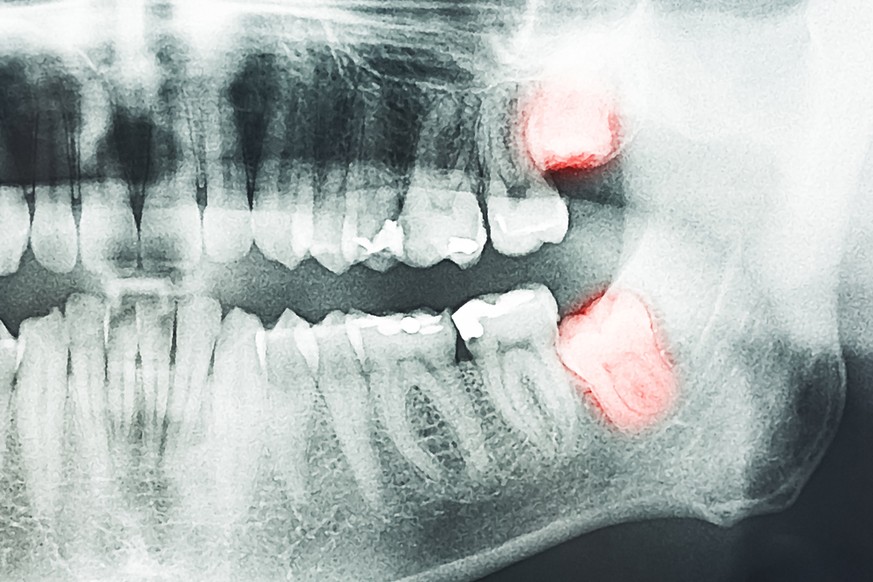

Weisheitszähne

Eigentlich haben Menschen 32 Zähne. Unsere Vorfahren hatten sogar 44 – aber sie hatten auch deutlich grössere Kiefer, die genügend Platz für die Kauwerkzeuge boten. Da die Menschheit aber seit langem über Techniken der Zerkleinerung und Zubereitung ihrer Nahrung verfügt, waren die vielen Backenzähne nicht mehr notwendig. Von den heute noch vorhandenen 32 Zähnen brechen zudem vier erst später – meist im Erwachsenenalter – durch das Zahnfleisch: die sogenannten Weisheitszähne oder dritten Molare. Oft fehlt aber der Platz für sie und sie müssen entfernt werden. Möglicherweise hat sich dieses Problem in moderner Zeit sogar verschärft, denn wegen der verbesserten Zahnhygiene verlieren wir nicht mehr schon früh Backenzähne. Früher schaffte der Zahnverlust Platz für die Nachzügler.